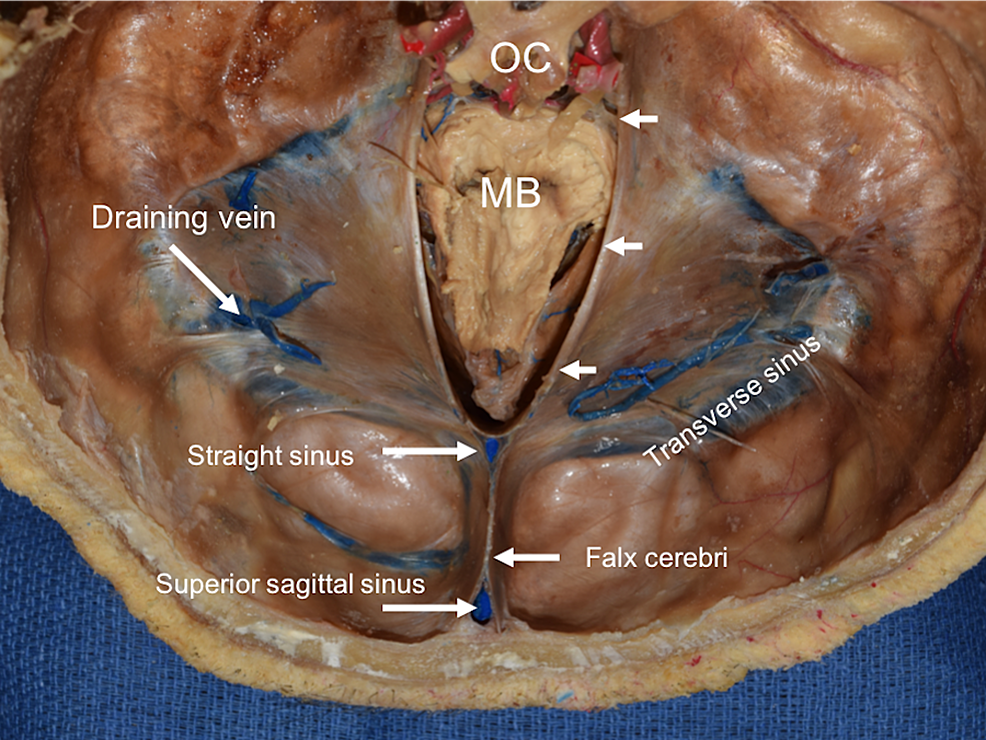

Label A-D